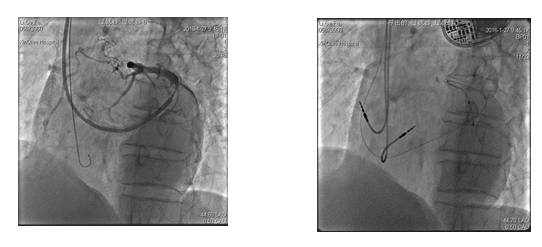

二、左心室心内膜起搏

[1]

◆2011年Lau等率先报道的左心室心内膜起搏

◆心室激动的传导顺序由心内膜向心外膜传导

◆ALSYNC是一项多中心、非对照、前瞻性临床研究,共纳入138例传统植入电极失败或无应答的患者,采用左室心内膜起搏技术并随访至少12个月发现,电极植入成功率为90%

优势

◆左心室电极植入成功率高

◆起搏阈值明显降低

◆主动固定电极有较好的稳定性

◆降低膈神经刺激,更换起搏部位简单直接

◆有更多的起搏点选择

◆更符合生理情况,减少心律失常的发生率

存在问题

◆血栓形成及栓塞并发症,需要长期抗凝治疗

◆电极潜在的对二尖瓣功能的影响

◆存在与二尖瓣相关的感染性心内膜炎的风险

◆手术难度较高